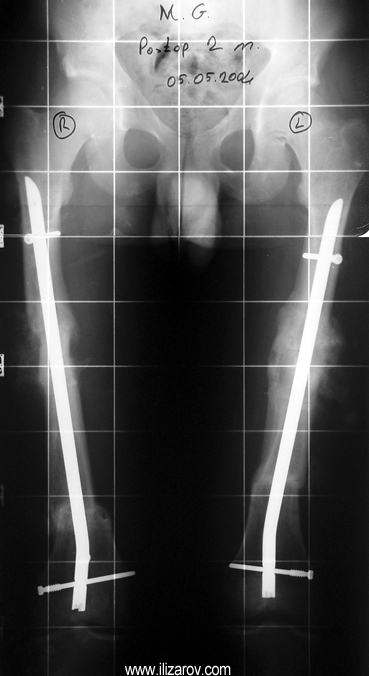

In hypophosohatemic rickets, abnormal bone findings become evident after 1 year of age; there are short stature and deformities around the knee (bilateral genu valgum or varum, tibial torsion, deformity at tibia and femur, ‘windswept’ deformity).

Because the deformity caused by hypophosphatemic rickets is very close to the growth plate, a significant deformity and malalignment occurs. For that reason, more than one deformity centers (CORA) are found at preoperative evaluation, and osteotomy at more than one level is required to correct the deformity. The most frequently used methods to correct the deformity are acute or gradual deformity correction using the Ilizarov method or unilateral external fixator. In the ‘fixator assisted nailing’ technique, which is applied in our department, the deformity is corrected in an acute fashion with the help of an external fixator, and the extremity is stabilized by an intramedullaru nail. The external fixator is removed before the end of the surgery if no gradual lengthening is planned postoperatively. If lengthening (over nail) is planned, the fixator is removed after the completion of the lengthening procedure. As a result, the risk of pin tract infection is eliminated, correction loss and relapsing of the deformity (which are important problems in the treatment of hypophosphatemic rickets) are avoided, eary motion and full weight bearing are allowed, and comfortability of the patient is improved because the duration with external fixator is decreased.

Case 2